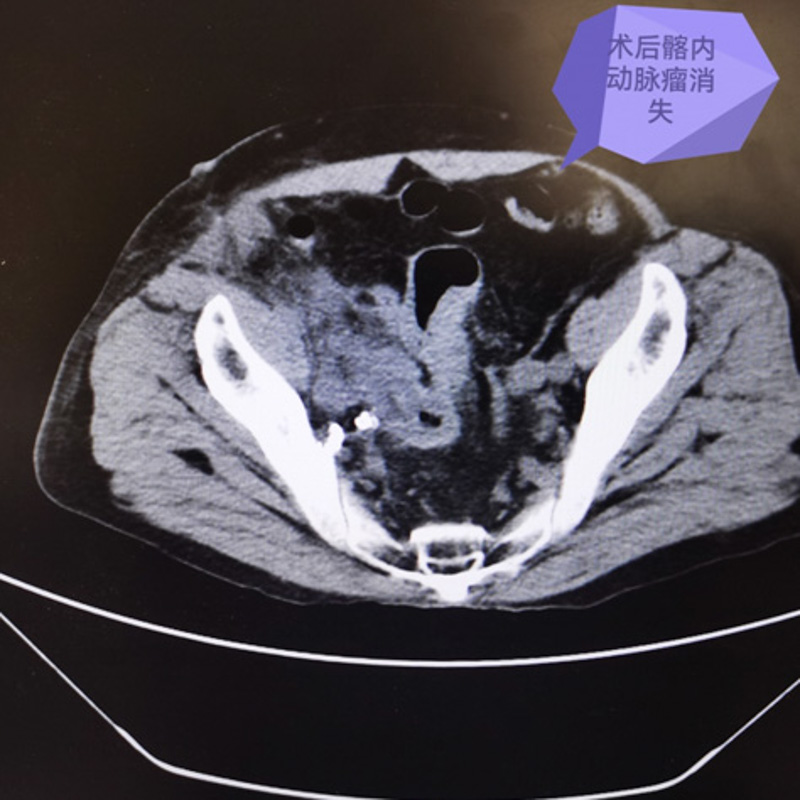

最終,專家們決定采用腹腔鏡下假性動(dòng)脈瘤切除手術(shù),再在腹部切開小切口取出“炸彈”。

手術(shù)如期進(jìn)行,血管外科主任霍鑫博士團(tuán)隊(duì)首先利用腹腔鏡小心翼翼將髂動(dòng)脈,髂靜脈,右輸尿管及粘連的腸道等組織與假性動(dòng)脈瘤分離。結(jié)扎髂內(nèi)動(dòng)脈分支后,再在右側(cè)腹部切開8cm切口,取出巨大假性動(dòng)脈瘤,手術(shù)完美收官。

術(shù)后賈老伯在醫(yī)護(hù)人員的照料下漸恢復(fù)良好,大小便困難的癥狀也消失了,他非常高興,對(duì)柳州市人民醫(yī)院醫(yī)護(hù)人員高超的技術(shù)贊嘆不已。一周后,患者便成功出院,回歸正常生活。